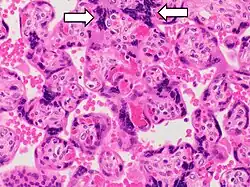

The syncytiotrophoblast (from the Greek 'syn'- "together"; 'cytio'- "of cells"; 'tropho'- "nutrition"; 'blast'- "bud") is the epithelial covering of the highly vascular embryonic placental villi, which invades the wall of the uterus to establish nutrient circulation between the embryo and the mother. It is a multinucleate, terminally differentiated syncytium, extending to 13 cm.

It is the outer layer of the trophoblasts and actively invades the uterine wall, during implantation, rupturing maternal capillaries and thus establishing an interface between maternal blood and embryonic extracellular fluid, facilitating passive exchange of material between the mother and the embryo.